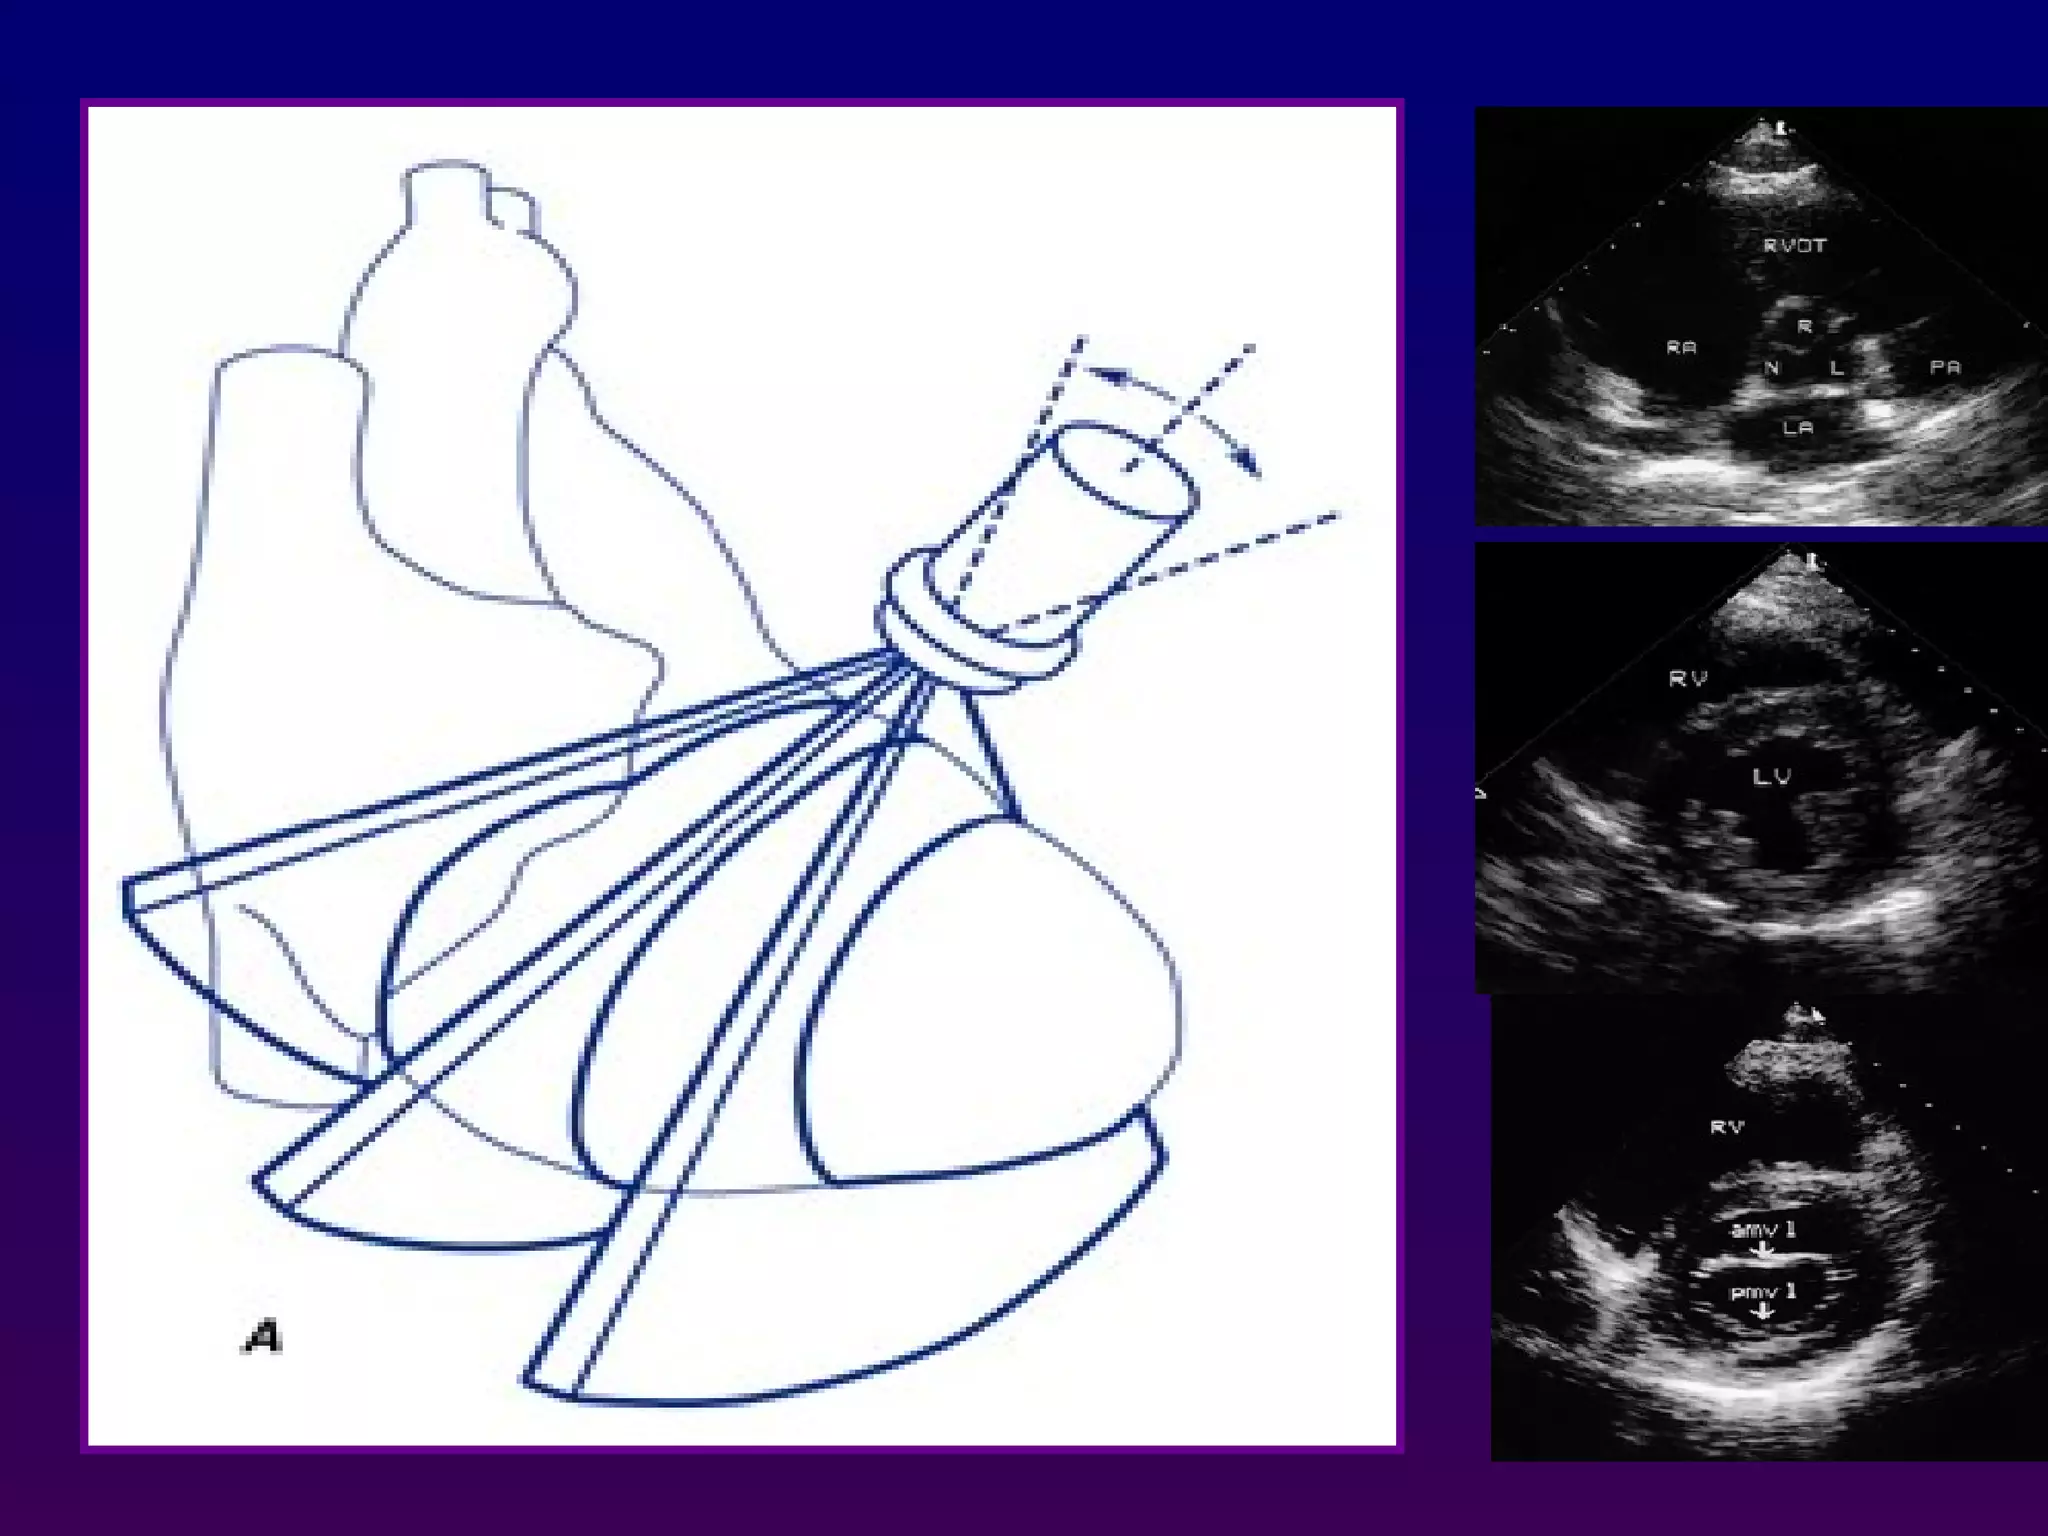

Each immage is determined by:

-The transducer position (parasternal, apical, subcostal,

suprasternal) Transducer position is altered by placing

the transducer at various locations on the thorax

-The tomographic view (long axis, short axis, 4- chamber,

5 chamber(.

which is often manipulated by a combination of angulation

and rotation of the transducer from the same position.

Each immage isdetermined by: -The transducer position (parasternal, apical, subcostal, suprasternal) Transducer position is altered by placing the transducer at various locations on the thorax -The tomographic view (long axis, short axis, 4- chamber, 5 chamber(. which is often manipulated by a combination of angulation and rotation of the transducer from the same position. LOOK TO THE DIRECTION OF THE ULTRASOUND BEAM

From the PLA orientation, a 90° clockwise rotation of

the transducer with superior and inferior

transducer manipulations permits delineation of the

parasternal short axis (PSA) views:

-At the base (aortic valve) view

-Mid (mitral valve ) view

-Mid ( papillary muscle) view

-And apical levels view

Parasternal short axis

70°to 110° clockwise

a 90° clockwise rotation

From the PLAorientation, a 90° clockwise rotation of the transducer with superior and inferior transducer manipulations permits delineation of the parasternal short axis (PSA) views: -At the base (aortic valve) view -Mid (mitral valve ) view -Mid ( papillary muscle) view -And apical levels view Parasternal short axis 70°to 110° clockwise

Parasternal short axis a90° clockwise rotation